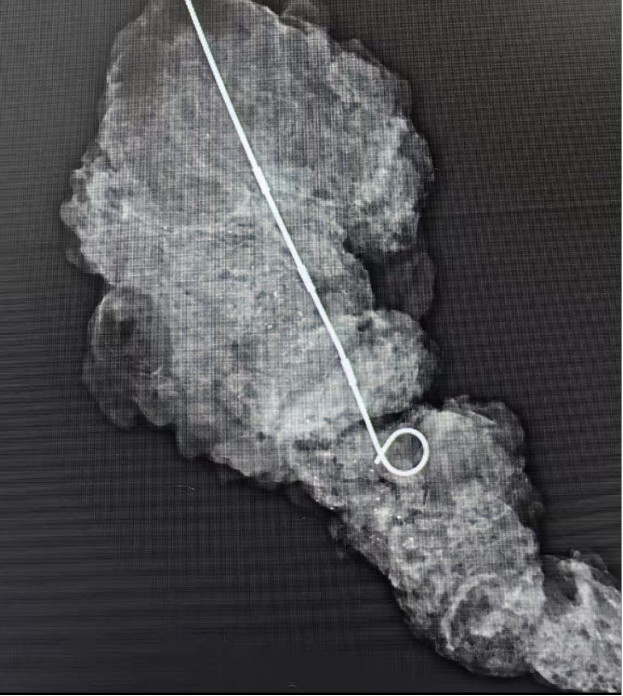

术中钼靶:粤西地区唯一配备专用术中钼靶设备,手术中实时进行钼靶摄片,如同装上“精准导航”,确保包含钙化灶在内的病变组织被完整、精确切除,避免遗漏或过度损伤。

▲术中钼靶摄片精准切除钙化灶